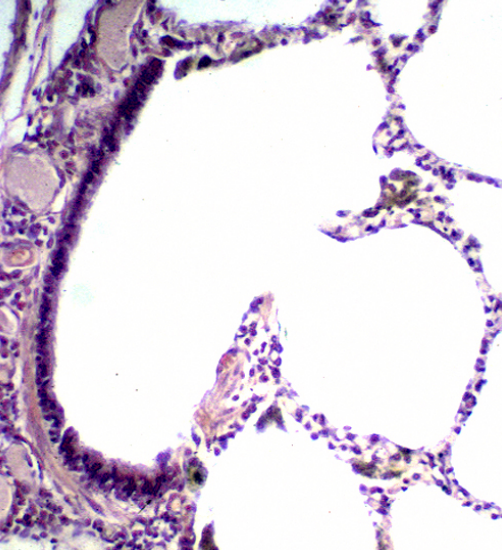

Identify the airway

Bronchus

This is a

bronchiole

Why is this a

respiratory

bronchiole?

the

airway is open to

alveolar gas

exchange

surfaces.

Identify the cells of the

alveolar septum